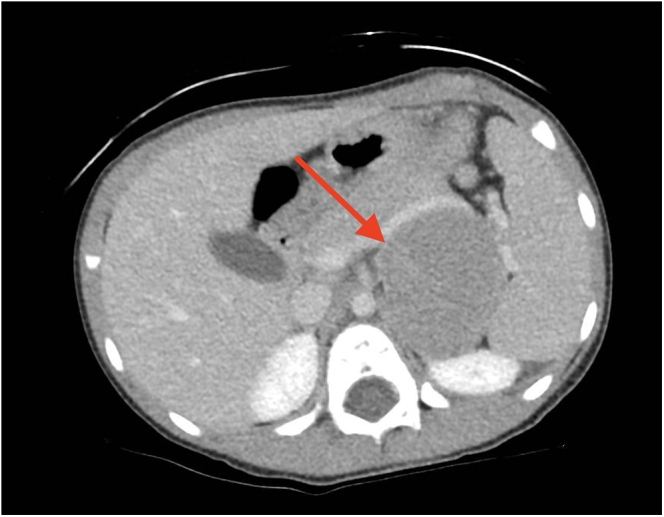

Summary: We report a 3.7-year-old female who presented with clinical features of premature adrenarche. Workup revealed significantly elevated androgen levels and advanced bone maturation, prompting abdominal imaging that identified a 6.0 cm adrenal mass. She underwent unilateral adrenalectomy, and subsequent histopathology revealed a benign oncocytic adrenocortical adenoma. Post-adrenalectomy, androgen levels returned to pre-pubertal levels. A review of the literature on pediatric oncocytic adrenocortical neoplasms (OANs) is presented, and we add our case to the growing data of this rare disease in the pediatric population.

Learning points: A high index of suspicion is necessary when encountering a prepubertal child with clinical signs of hyperandrogenism and advanced bone age. Oncocytic adrenocortical neoplasms are rare in children and are often benign, although they can be malignant or of uncertain malignant potential. Adrenalectomy is necessary for histopathological diagnosis and definitive treatment. Pediatric oncocytic adrenocortical neoplasms are typically associated with elevated androgens; however, they can have a variety of other abnormal hormonal profiles at presentation. Return to normal hormonal levels is common post-adrenalectomy.